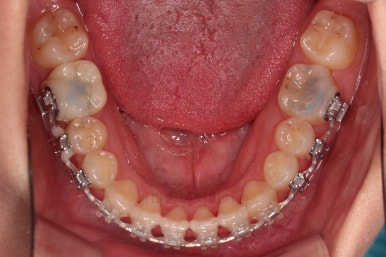

마찬가지로 초진 시 입안의 모습인데요.

위아래 앞니가 삐뚤고, 송곳니는 덧니처럼 불룩 튀어나가 있네요.

위아래 앞니는 안으로 굽어 들어와 있는 옥니(뻐드렁니 반대) 양상이었고요.

그리고 마무리 때 디테일에 문제가 생길 수 있는 부분인데, 윗니 대문니(가장 중간 치아)와 송곳니 사이의 치아를 작은 앞니라고 하는데요.

이 작은 앞니가 가져야 될 크기보다 더 작은 양상이었습니다.

이런 치아를 왜소치라교 표현합니다.

처음 장치를 부착한 모습인데요.

이번 환자분이 부산옥니교정에 사용한 장치는 엠파워 클리어라고 하는 자가결찰 세라믹 장치였습니다.

철사를 잡아주는 캡(결찰)이 브라켓에 달려있어 스스로 묶고 풀고가 가능한(자가) 세라믹 재질의 장치라는 뜻인데요.